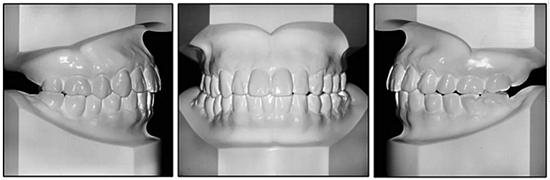

36歲;女性;尋求下頜左后方區(qū)域間隙管理的建議(圖1和圖2),通過(guò)治療獲得了良好的牙頜面效果(圖3和圖4)。她被診斷患有骨性I類(lèi)和代償性牙性II類(lèi)錯(cuò)合畸形,并且上頜左側(cè)尖牙缺失(圖1和2)。大約七年前,由于不可修復(fù)的齲齒,拔除了下頜左側(cè)第一和第二磨牙(圖5)。37相鄰的第三磨牙向近中移動(dòng)并傾斜入間隙,導(dǎo)致無(wú)牙頜間隙減小至約14 mm(圖2和圖5)。臨床和影像學(xué)評(píng)估顯示多發(fā)性齲損和在下頜右側(cè)567處有一不良的固定橋修復(fù)體(圖1和5)。此外,下頜左中切牙缺失,造成下頜中線(xiàn)向左側(cè)偏移約3 mm(圖1和圖2)?;颊咦栽V,她的右上第一前磨牙和左上尖牙在13歲時(shí)由其家庭牙醫(yī)拔除,因?yàn)樗鼈儽蛔枞筋a側(cè)萌出(圖1)。上頜第二磨牙缺失(未知病因),并且相鄰的第三磨牙已經(jīng)轉(zhuǎn)移到第二磨牙間隙中。如補(bǔ)充材料所示,美國(guó)正畸學(xué)差異指數(shù)DI是28分。種植體部位(下頜左側(cè)和右側(cè)第一磨牙)由于復(fù)雜性得到額外4分(補(bǔ)充材料)。

圖2. 治療前牙齒模型